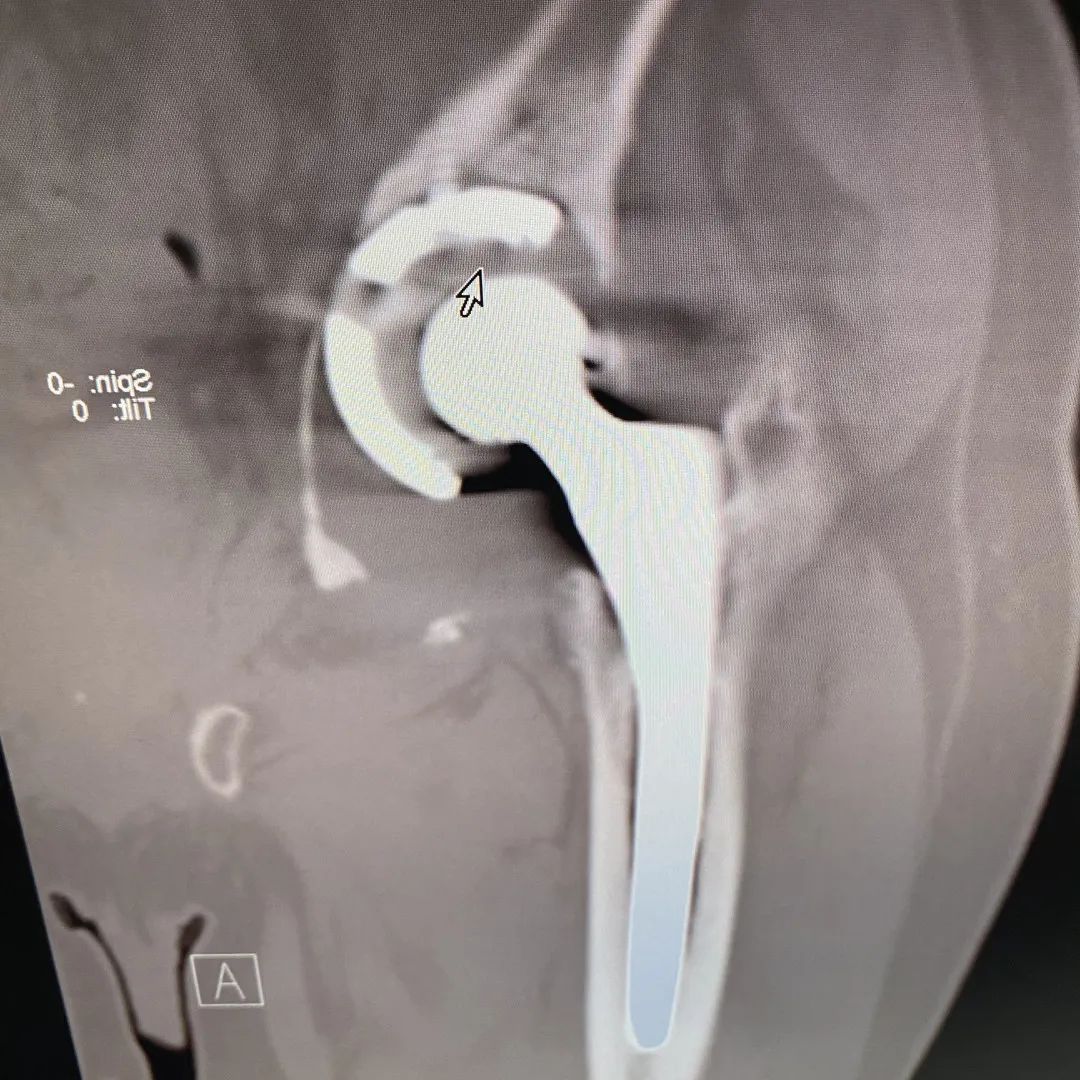

经过骨科团队详细检查后,认为“患者髋部疼痛及功能障碍是由于人工关节髋臼松动假体松动导致。人工髋臼移位明显,伴随髋臼周围大量骨溶解、骨吸收。重建稳固的髋臼是手术的首要任务,大量骨溶解、骨吸收给手术带来相当大的挑战。

术前,手术团队运用3D打印技术,精准打印患者骨缺损情况,并个体化设计手术方案,选择人工假体组件;体外模拟手术,以确保手术过程精准、顺利进行。

术前照片

3D设计照片